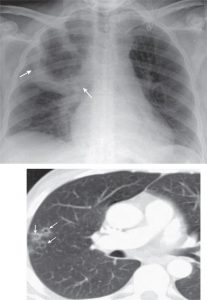

شکل بعدي يک لوبار نومونيا به علت نوموکوک است.

چون برونش اصلي سمت راست هم کوتاه تر و هم مستقيم تر است، بيشتر آسپيريشن نومونيا در اين سمت است.

تصوير صفحه بعد يک لوبار نومونيا با يک سي تي اسکن از برش آگزيال است.